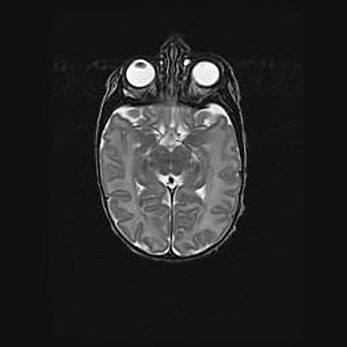

Неполная лизэнцефалия (пахигирия). Открытая гидроцефалия.

Возраст: 17 дней

Вес: 3110 г

Пол: мужской

Окружность головы: 33,5 см

Срок гестации: 35-36 недель

Лизэнцефалия—недоразвитие корковой пластинки и мозговых извилин в результате нарушения миграции нейронов коры. Поверхность мозговых полушарий гладкая. Микроскопически выявляется отсутствие нормальных слоев коры и скопление групп нейронов в подкорковом белом веществе.

Пахигирия—уменьшение числа вторичных извилин. В пораженном полушарии нервные клетки образуют толстый недифференцированный слой с неправильно расположенными нервными волокнами и группами гетеротопных клеток. Нервные клетки незрелые. Белое вещество истончено. При этом нередко аномально развит корково-спинномозговой путь.